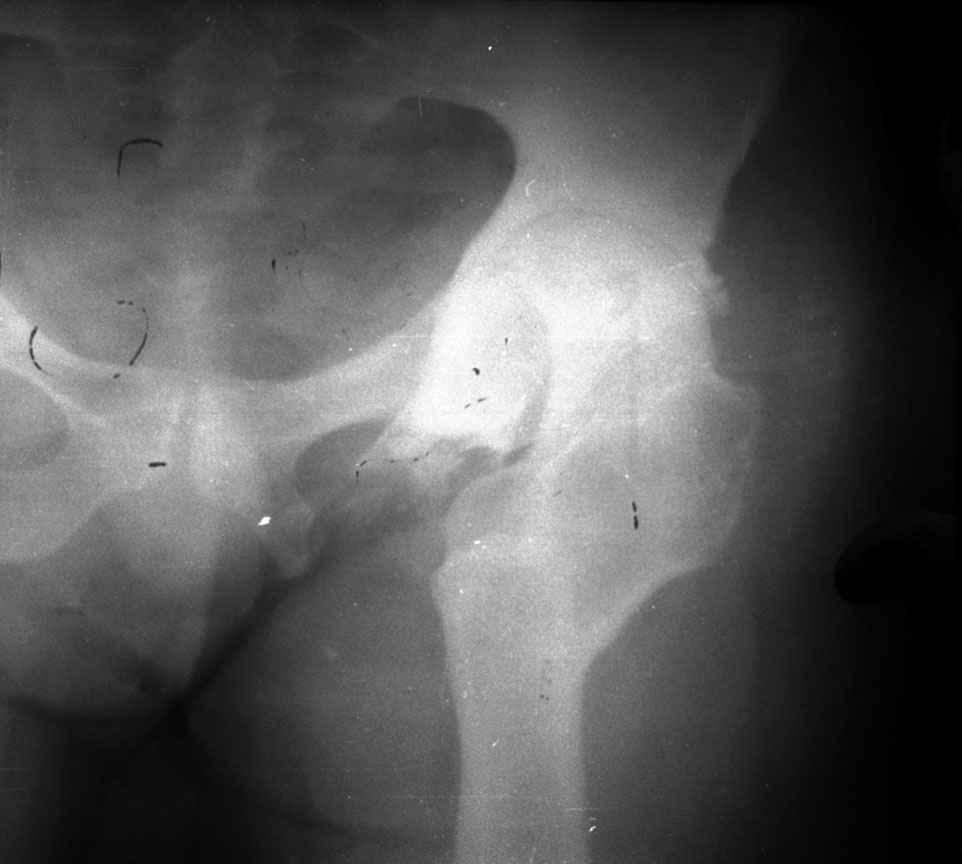

Moghno i tak kak sdelali my: pelvic support + tibial and equinus correction .

Слайд 1

Слайд 2

Слайд 3

Слайд 4

Devushka predstavlennaya na snimke nachala s LLD 9 cm, valgus deformation of the tibia, huge Trendelenburg( vidno na snimke).

Seichas : no LLD ,no Trendelenburg, reasonable hip motion.A samoe glavnoe ei ne predstoit kaghdye 10-15 let delat revision THR.

остеотомии. Я представил Р-граммы больных с неудачными р-ми после остеотомий.

Эндопротезирование у них было на порядок сложнее в отличие от артропластики без проведения остеотомии.